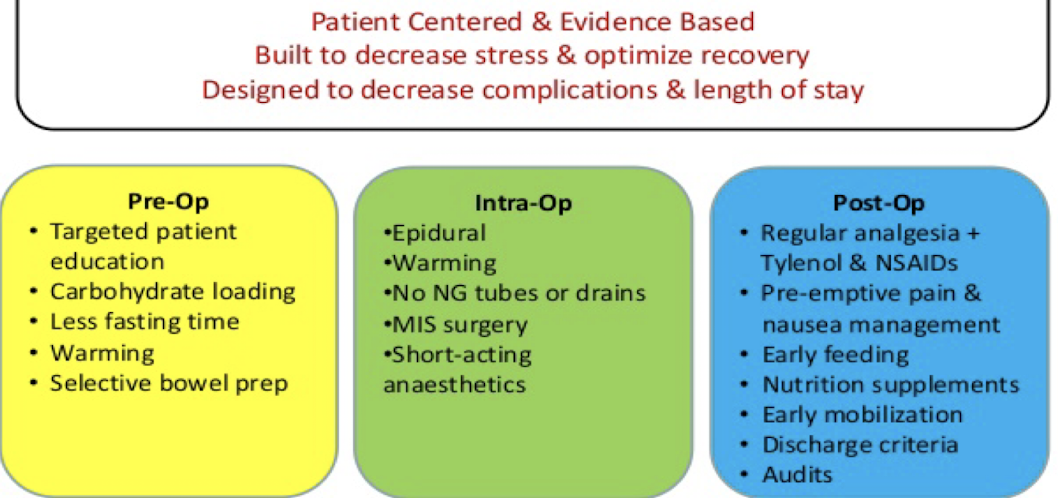

ERAS (Enhanced Recovery After Surgery)

Discharge criteria

• Pain control (PO meds)

• Wound concerns/Bleeding

• Tolerating PO (oral intake) without N/V

• Mobility/Safety

• GI? Flatus vs BM (especially general surgery)

• Any things specific to your service!!!

• Work with RN Case Managers, Social Workers

Post-op pain control

Trend towards:

• Regional blocks

• Epidural/Spinal blocks

• Multimodal pain control (APAP, Gabapentin)

• NSAIDs/Toradol

• Local infiltration

Trend AWAY from use of opioids (increased risk tolerance)